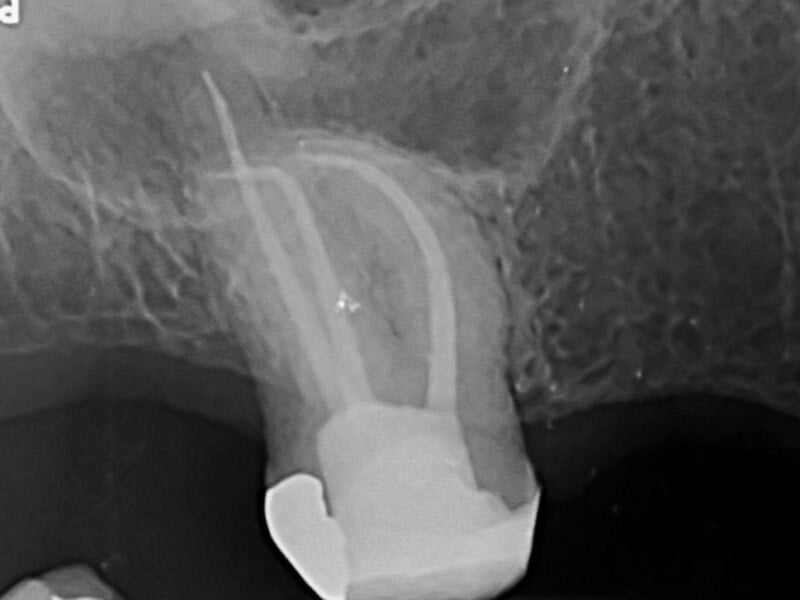

- The endodontist makes an opening through the crown of the tooth. Very small instruments are used to remove the pulp from the pulp chamber and root canals, and then to clean & shape the space for filling.

- After the space is cleaned and shaped the endodontist fills the root canals with a biocompatible material, usually a rubber-like material called “gutta-percha.” The gutta-percha is placed with a cement to ensure complete sealing of the root canals. A filling is then placed to close the opening in the crown of the tooth.